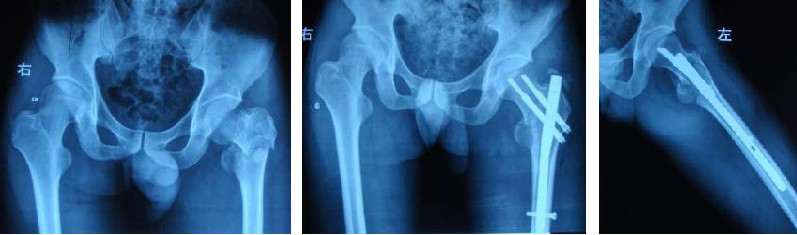

Le clou Gamma unit fermement le fémur supérieur et le col fémoral grâce à la combinaison du clou intramédullaire et de la vis de tension, et le clou intramédullaire est fixé par le clou autobloquant distal, qui empêche la rotation et le raccourcissement du déplacement et assure une fixation fiable.

Un appareil intégré idéal pour les fractures intertrochantériennes instables du fémur.

Il fixe fermement la tête et le col fémoral et empêche la rotation de l'extrémité de la fracture.

Empêche les complications telles que l'effondrement dû à la résorption osseuse après la perte du support médial, la déformation en inversion et la découpe de la tête fémorale avec l'insert.

Convient à presque toutes les fractures intertrochantériennes, en particulier pour les fractures instables (par exemple les fractures intertrochantériennes antérieures) et l'ostéoporose combinée.